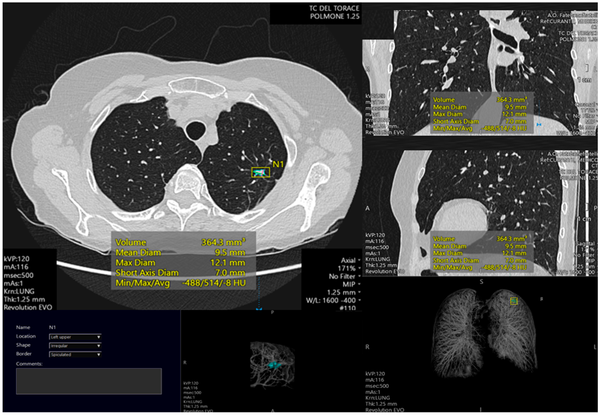

- Công nghệ hình ảnh hiện đại: PET/CT, SPECT/CT, SPECT… cho phép phát hiện tế bào ung thư ở giai đoạn rất sớm. PET/CT thế hệ mới chỉ mất 30 giây để quét toàn thân và dùng liều phóng xạ thấp, an toàn hơn.

- Trí tuệ nhân tạo (AI): Hỗ trợ phân tích hình ảnh CT, nội soi và mô bệnh học với độ chính xác cao, đang được triển khai tại các bệnh viện lớn như Bạch Mai.